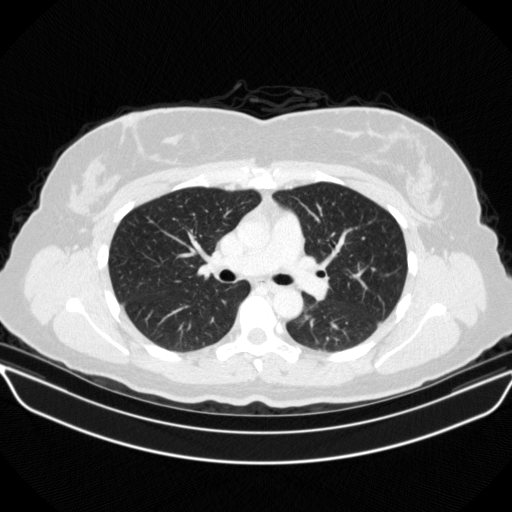

Original NATIVE CT scan (input)

Full window (WL 1023.5, WW 4095 β†’ Low βˆ’1024, High +3071)

Actual HU range: [-1024.0, 1296.0]

Lung window (WL -600, WW 1500 β†’ Low βˆ’1350, High +150)

Actual HU range: [-1024.0, 150.0]

Mediastinum window (WL 40, WW 400 β†’ Low βˆ’160, High +240)

Actual HU range: [-160.0, 240.0]